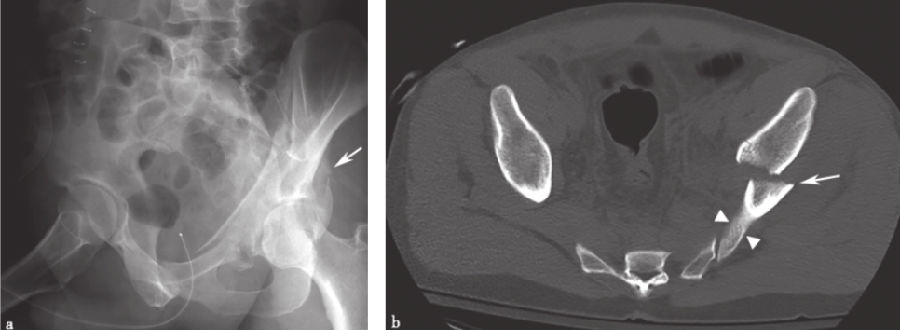

5、孤立后壁髋臼骨折:

孤立后壁髋臼骨折(图14)是髋臼骨折最常见的类型之一,发生率为27%。因此,髂坐线完整时,不考虑横行后壁骨折的分型。然而,髂坐线的破坏可能会或不会作为粉碎后壁组分的延伸存在。斜Judet位X线片和CT有助于显示孤立后壁髋臼骨折。

图14 孤立后壁髋臼骨折a.骨盆正位X线片;b、c.双侧斜位骨盆X线片;d、e.轴向CT扫描;f.矢状面CT重建。直线箭头示骨折部位,弯曲的箭头示后壁骨折块。